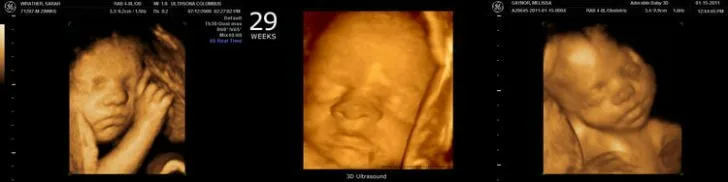

🔸 Медицинские обследования и УЗИ

На 29 неделе плановых медицинских обследований обычно не назначается. УЗИ может быть рекомендовано врачом при необходимости, например, при повышенном тонусе матки или для контроля веса плода, особенно при многоплодной беременности, так как увеличение веса матери не всегда точно отражает развитие каждого из малышей. Врач может назначить дополнительные анализы или консультации при наличии каких-либо жалоб или отклонений от нормы.